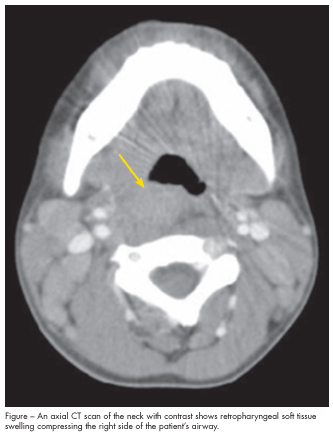

The patient was treated empirically with intravenous nafcillin and clindamycin; however, he continued to have high fevers, with temperatures up to 40.3ºC (104ºF). On hospital day 4, the antibiotics were switched to ampicillin/sulbactam and vancomycin because of concern for resistant pneumococci and methicillin-resistant Staphylococcus aureus. The next day, a CT scan of the neck revealed midline and right-sided retropharyngeal soft tissue swelling from the skull base through C6, with a prevertebral phlegmon at C4 (Figure). Bilateral internal jugular chain and posterior triangle adenopathy was also noted, with the largest lymph node measuring 18 mm. No circumscribed abscess was seen. A second CT scan obtained 4 days later showed partial resolution of the prevertebral phlegmon and no abscess. An MRI scan of the head and neck confirmed these findings.